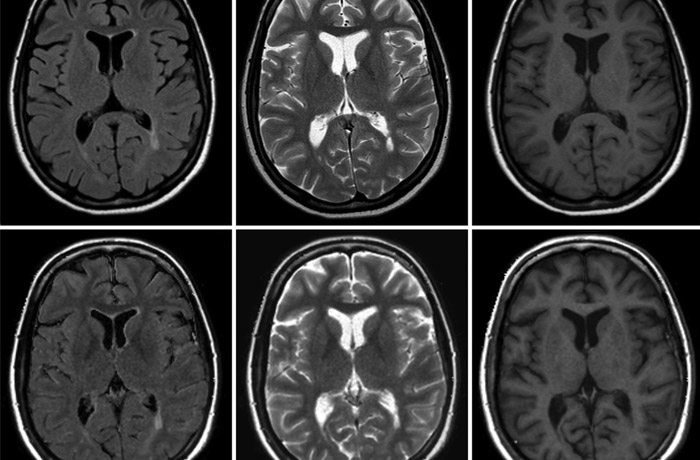

МРТ с контрастом – самый современный и достоверный способ проверка состояния здоровья внутренних органов и всего организма человека. Данное исследование применяется не только в зарубежной, но и отечественной медицинской практике. Магнитно-резонансная томография с контрастом применяется с целью выявления патологий и тяжелых заболеваний. Благодаря данному методу, имеется возможность визуализации даже глубоко расположенных тканей.

Качество снимков в данном случае, практически не отличить от реальных фотографий, благодаря чему имеется возможность разглядеть каждый участок максимально эффективно.

Чтобы получить наиболее качественный и достоверный результат во время исследования специалистом назначается специальный препарат на основе гадолиния. Большинство людей пугаются использования подобного дополнительного контраста и думают, что он может существенным образом сказаться на здоровье. На самом деле эти опасения безосновательны, ведь это всего лишь красильное вещество, использующееся для визуализации структуры человеческого организма.